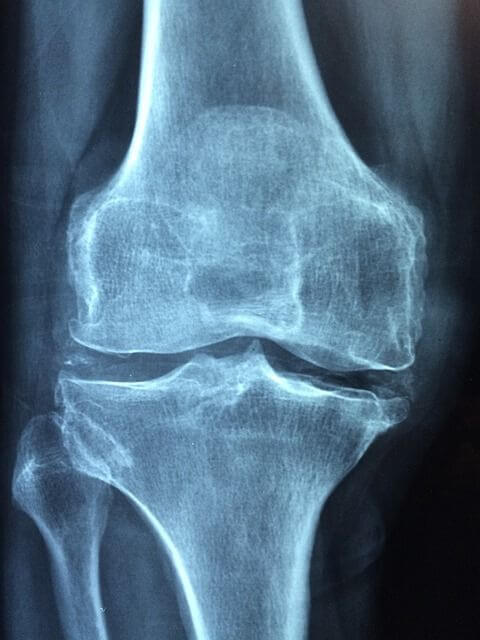

베이커 낭종은 퇴행성 무릎관절염, 반월상연골 파열과 같은 무릎의 질환과 큰 관련이 있습니다. 또한 류마티스성 관절염과 같은 염증성 질환이 있으면 인대의 이완도가 변하여 베이커 낭종이 생길 수도 있습니다.베이커 낭종의 임상 증상

베이커 낭종을 확인하기 위해선 임상적인 평가가 주로 사용됩니다. 대부분의 낭종은 반막양근과 종아리근육의 안쪽 머리 사이에 위치해 있으며, 낭종이 커진 경우에는 육안으로 보거나 만질 수 있습니다, 대부분의 경우 X선(XR)은 정상으로 나타납니다. MRI는 특별히 필요하지 않으며,